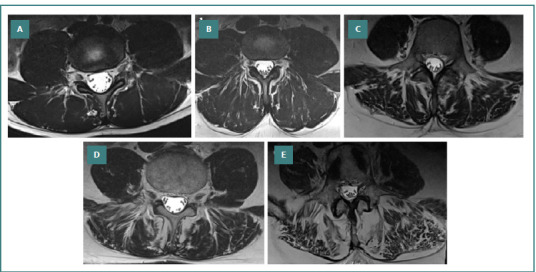

Laminectomy is a widely used surgical approach in patients with spinal canal stenosis but can result in biomechanical changes leading to iatrogenic spondylolisthesis. While some factors, such as surgical technique and achievement of spinal stability, are key contributors, patient-specific factors remain underexplored. Our study included 64 patients with diagnosed iatrogenic spondylolisthesis following previous spinal surgery. They were stratified into male and female groups, and clinical parameters such as the body mass index (BMI), fatty infiltration of the paraspinal muscles (assessed via Goutallier classification), pain scores (Visual Analogue Scale - VAS), and functional outcomes (Oswestry Disability Index - ODI) were analyzed pre-and postoperatively. The cohort consisted of 19 men and 45 women, with a mean age of 63.7 ± 10.82 years. There was a statistically significant difference in BMI, with higher values in women than men (30.16 ± 2.73 vs. 28.11 ± 2.71, P = 0.0078). Fatty infiltration of the paraspinal muscles was also more pronounced in women, with significant differences observed in Goutallier grades 2 and 3 (P = 0.007). While no differences were noted in surgery duration or hospital stay, males experienced greater intraoperative blood loss (P = 0.0442). Both groups had similar short- and mid-term pain and functional improvement, with no statistically significant differences in the VAS or ODI scores. In conclusion, patients with iatrogenic spondylolisthesis showed sex-based differences in BMI and fatty infiltration of the paraspinal muscles in patients. These factors did not influence short- and mid-term functional recovery but may play a key role in disease progression and surgical outcomes.